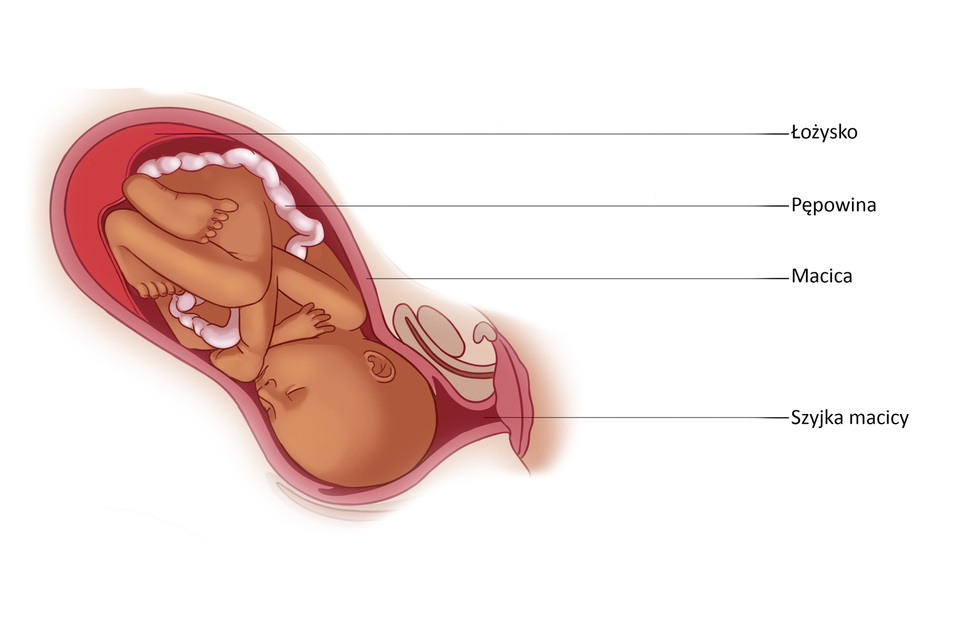

Pępowina i łożysko

9 miesiąc | 50 | Tęczówka oka ma zabarwienie niebieskie. Łożysko pracuje z maksymalną wydajnością (70% przenoszonych przez nie składników odżywczych trafia do mózgu). W jelicie nagromadzona jest smółka. Płód przyjmuje pozycję główkową - jest gotowy do porodu. ![]() Źródło: Englishsquare.pl Sp. z o. o., licencja: CC BY-SA 3.0. |

W przebiegu porodu wyróżnia się trzy fazy: rozwierania, wypierania i łożyskową.

Galeria przedstawiająca fazy porodu: